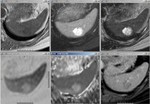

[画像診断]脾のリンパ管腫疑い 2010-07-05